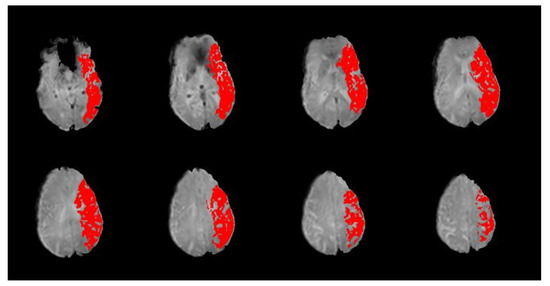

Figure 2.

Sample slices from a participant’s PWI scan with time-to-peak (TTP) map overlay. A TTP delay of ≥4 s is shown in red. Per the slices included here, this participant would be coded as having a perfusion deficit present in all four regions of the MCA territory (frontal (MCA-F), temporal (MCA-T), parietal (MCA-P), and insular (MCA-I)).